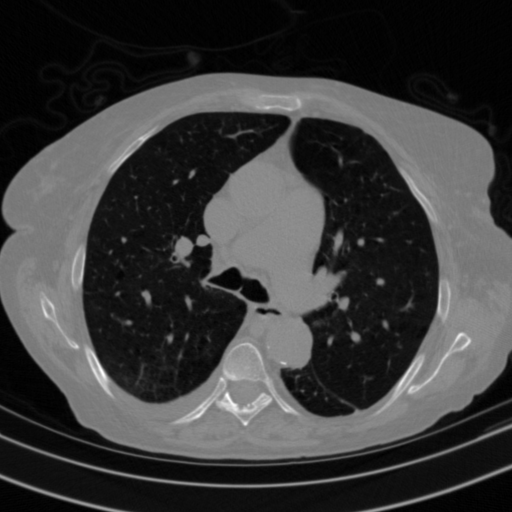

Generated VENOUS CT scan (A→B translation)

Lung window (WL -600, WW 1500 β†’ Low βˆ’1350, High +150)

Actual HU range: [-1201.8, 150.0]